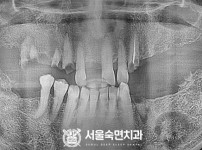

임플란트-전후사진4

치과를-선택할-때-꼭-확인하세요-서울숙면치과-임플란트-전후사진